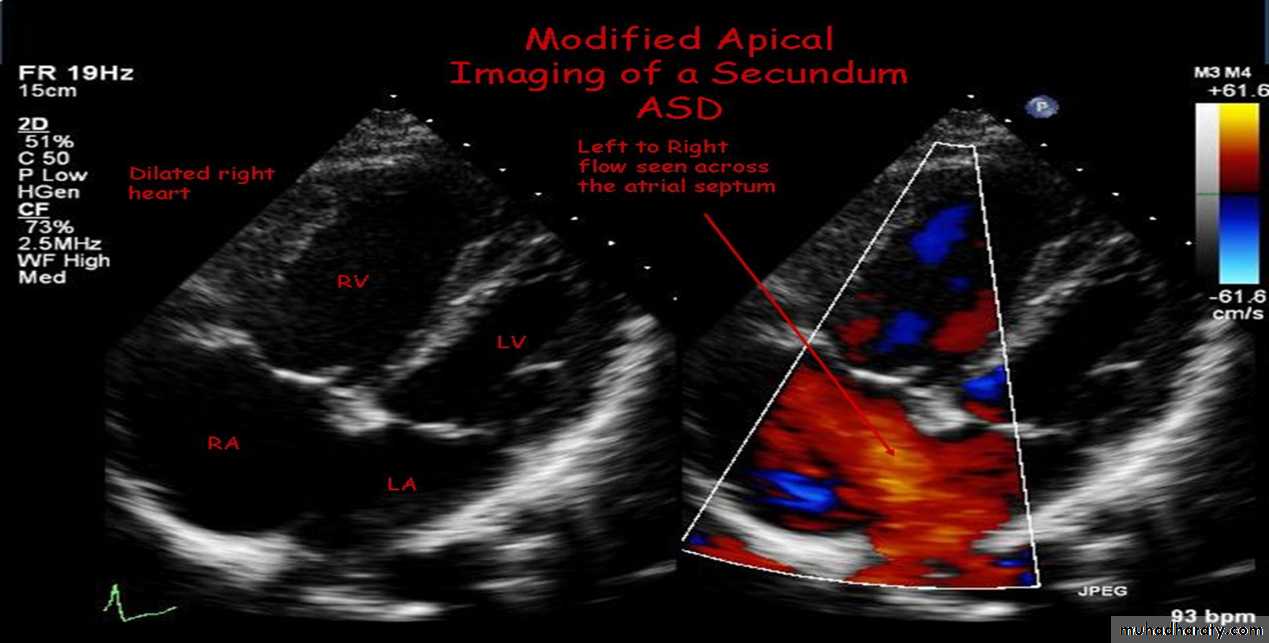

3-Echocardiography

The location and size of the atrial defect are readily appreciated by two-dimensional scanning . The shunt is confirmed by pulsed and color flow Doppler .